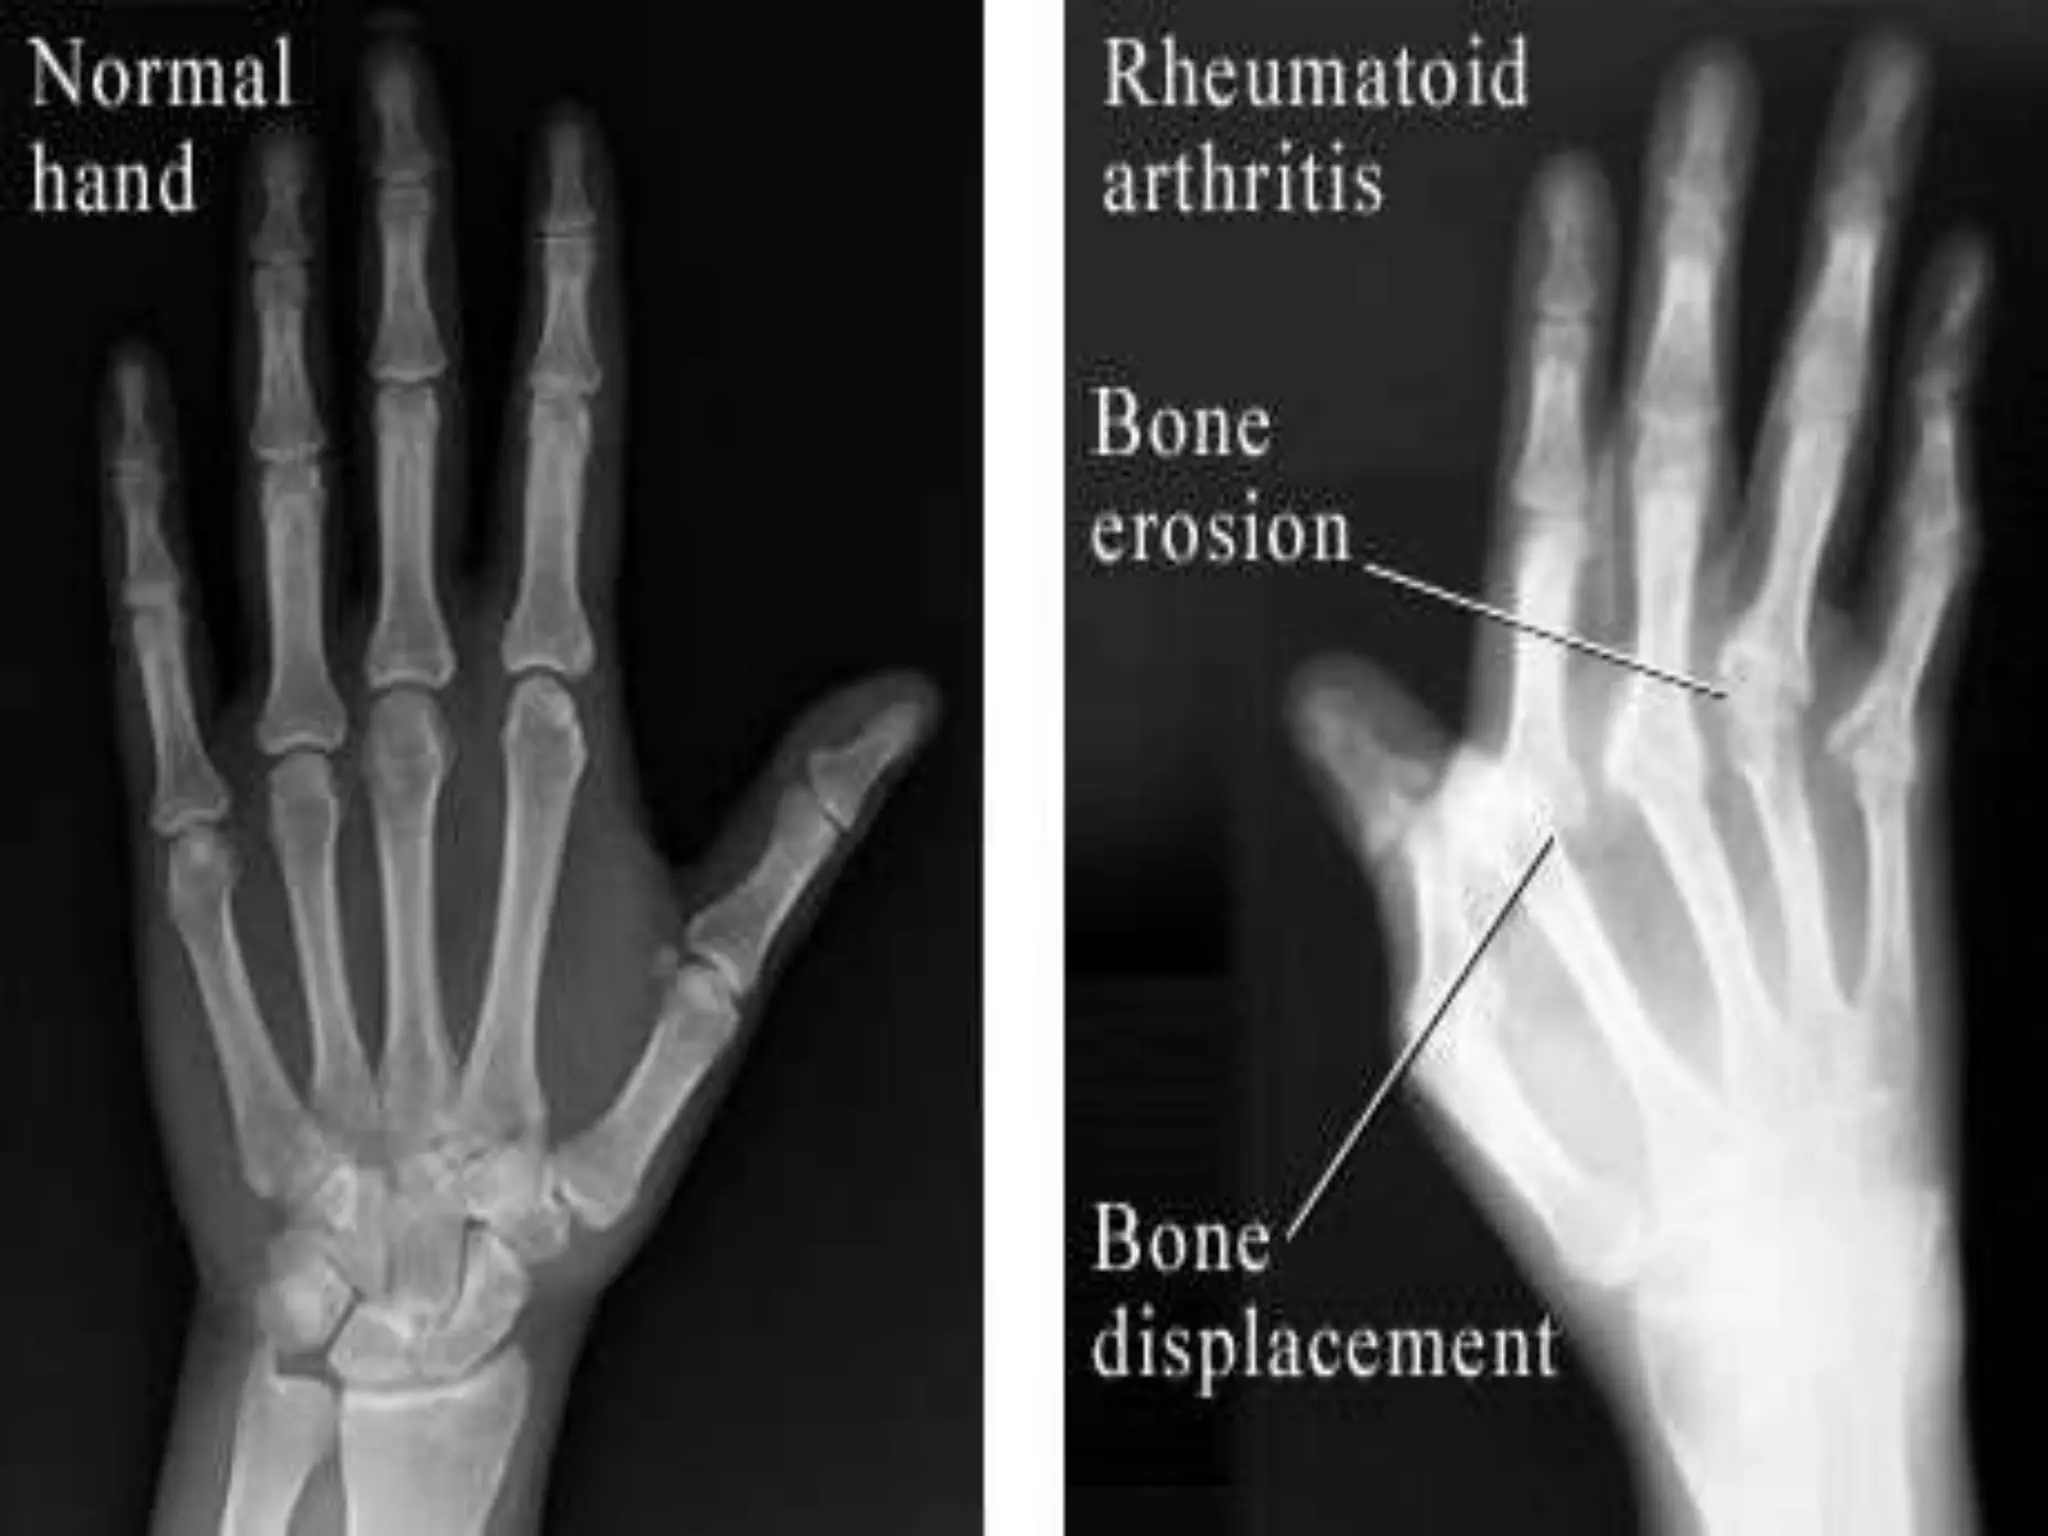

Radiologic examination-

• This consists of X rays of both hands and of the

affected joints. The following features may be

present:

• Reduced joint space

• Erosion articular margins

• Subchondral cysts

• Soft tissue swelling

Radiologic examination- • Thisconsists of X rays of both hands and of the affected joints. The following features may be present: • Reduced joint space • Erosion articular margins • Subchondral cysts • Soft tissue swelling